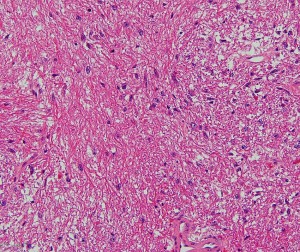

小児期の毛様細胞性星細胞腫

10才小児の小脳結節性毛様細胞性星細胞腫です。典型的な良性腫瘍として知られる毛様細胞性星細胞腫です。

HE染色です。左のように双極性突起を延ばす小型の核を有する充実性部分 compact part と,中央に見られるような細胞間に微小嚢胞変性と類粘液性基質がみられる海綿状部分 spongy partが混在する毛様細胞性星細胞腫に特徴的なbiphasic patternがみられます。右側の画像では小さな粘液基質を含みながらびまん性星細胞腫に類似する組織像が認められます。左の画像の矢印で示す赤い玉のようなものはeosinophilic granular bodiesです。